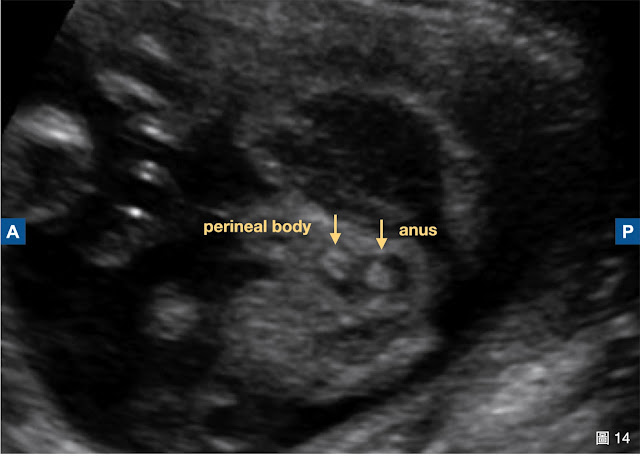

第二個陷阱是會陰體 (perineal body)。

有時,在肛門 target sign 前方,可見另一個很類似的標靶結構,那是會陰體。不可將它誤認為肛門 (圖 14)。

圖 14(台兒診所提供)

由圖 15 中可知,肛門的位置在 ischial tuberosity 假想連線的稍後方,而會陰體在稍前方。